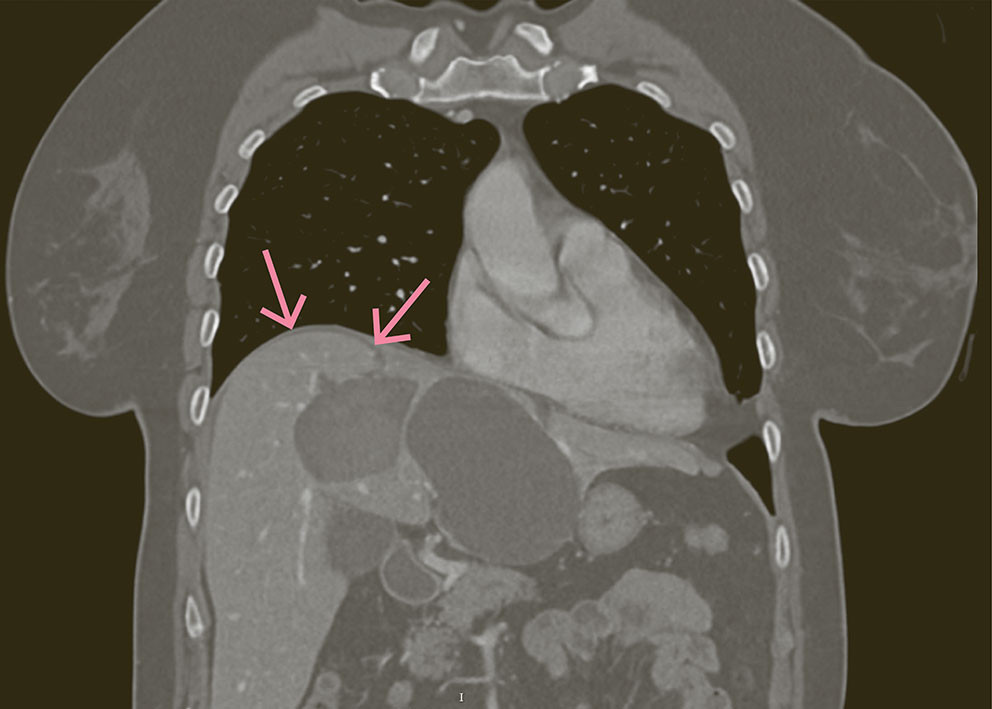

Pasienten ble tatt imot av traumeteam etter en sykkelulykke hvor hun landet med sykkelstyret mot den midtre delen av buken. Ved mottak var hun stabil, men diffust palpasjonsøm i buken. Traume-CT viste sannsynlig levercysteruptur.

Dagen etter ble hun laparoskopert grunnet økende peritonitt. Man fant blod i hepatorenale fossa og bekken samt en levercyste med ferske adheranser mot bukveggen. Tynntarmen var uten tegn til skade. Blakes-dren ble lagt i hepatorenale fossa (dren 1) og bekken (dren 2). Første postoperative dag var det kommet 50 mL på dren 1 med utseende som utvannet galle. Drensvæsken målte bilirubin 330 µmol/L, og amylasenivået var normalt. Pasienten hadde fremdeles økende smerter, og det ble derfor tatt MR lever med dinatriumgadoksetat for å utelukke lekkasje fra andre, ikke-visualiserte, skader. MR-undersøkelsen med hepatocyttspesifikk kontrast påviste gallelekkasje fra cysten i segment 4A og videre langs dren 1. Det kliniske bildet var dermed forenlig med veldrenert biliær peritonitt. Drensproduksjonen avtok gradvis, og drenet ble seponert dag 16 etter operasjonen.

Prevalensen av levercyster er 1–18 % (1). Traumatisk levercysteruptur er en sjelden, men aktuell differensialdiagnose ved akutt abdomen. I svært sjeldne tilfeller, som hos vår pasient, kan det oppstå biliær peritonitt dersom cysten kommuniserer med intrahepatiske galleveier (2). Biliær peritonitt etter en cysteruptur kan være en livstruende tilstand, og risikoen for cysteruptur øker med cystestørrelse. Kirurgisk lavage og drenasje er primærbehandlingen. Prognosen er generelt god, men enkelte fatale hendelser har vært rapportert. Dette rettferdiggjør ikke en anbefaling om forebyggende volumreduserende behandling hos pasienter med kjente levercyster (3).